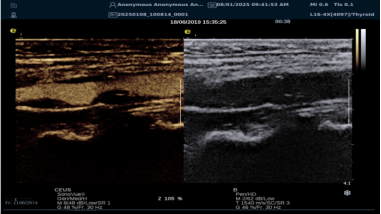

)独有超声造影 + 技术

银河官网医疗的造影 + 模式(CCI)利用脉冲反相、高质调幅技术与超宽频带探头,基于 iPlane?平台优化成像。优势包括:

image.png

? 实时 MVI 微血管造影可显示微循环,对斑块内微小血管单个气泡成像,强化血管轮廓显示血流轨迹,对斑块内新生血管评估和脑卒中预防意义重大。

? 对造影剂敏感度高,时空分辨率优,造影图像清晰,有效评估新生血管。

? 兼容多种造影剂,参数可调,支持动态存储与能量调节,操作简便。